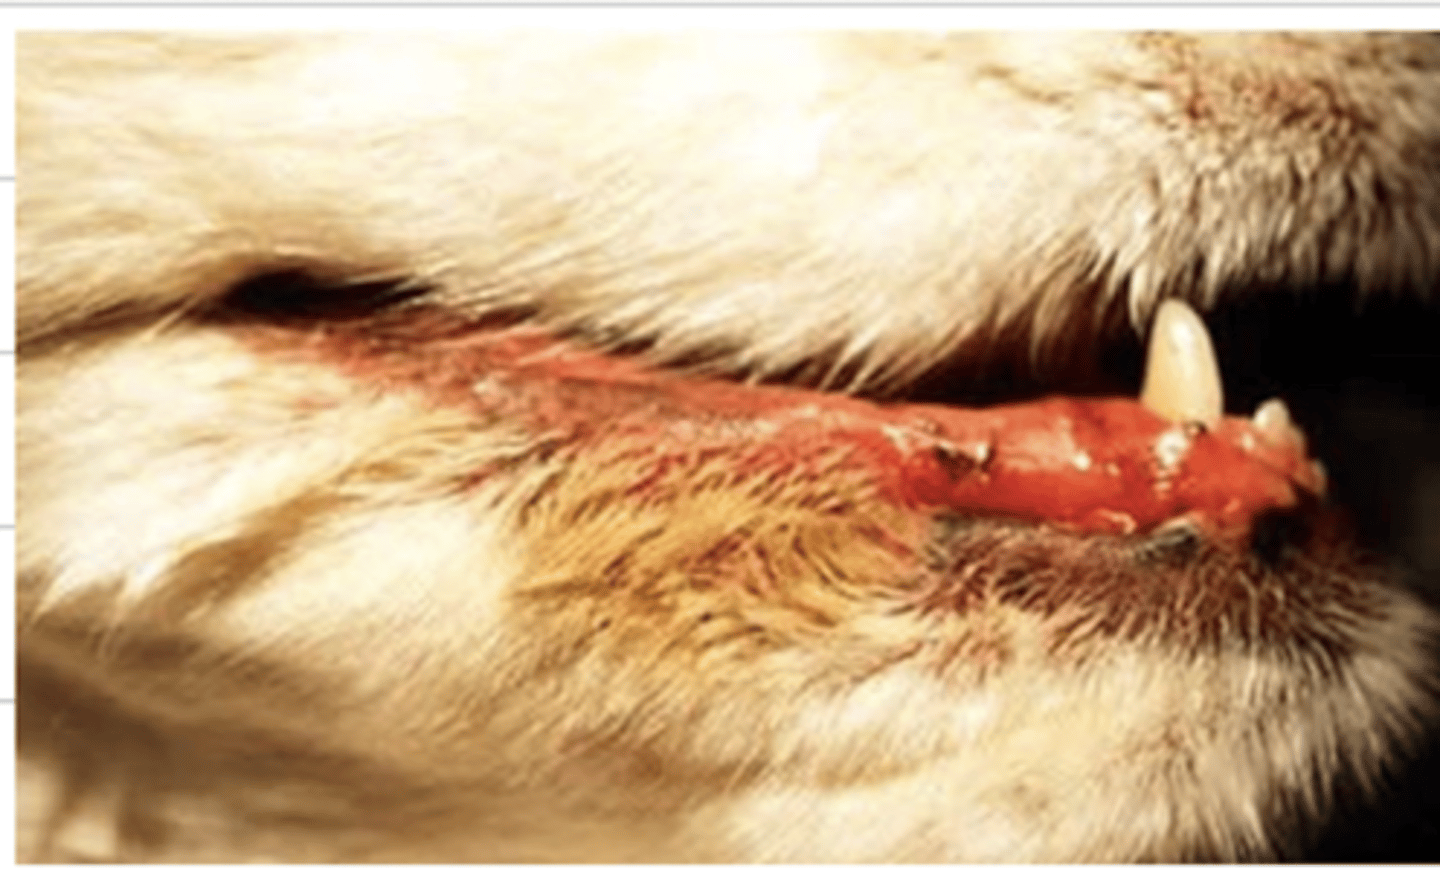

cheilitis

what is the medical tern for the condition of this dog?

cheilitis

what does this dog have wrong?

saint bernards, springer spaniels, bulldogs

(dogs with droopy cheeks)

what dog breeds are predisposed to cheilitis?

-poor oral hygiene

-inflammation of adjacent tissues

-chewing sharp objects/ foreign bodies

what can cause cheilitis?